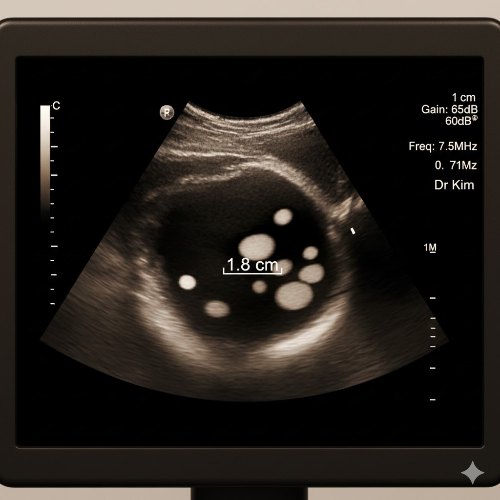

담석증은 간에서 만들어진 담즙이 담낭(쓸개) 안에서 딱딱하게 굳어 돌처럼 생기는 질환입니다.

| 담석의 크기가 3cm 이상 | 크기가 클수록 담낭암 발생 위험이 높아짐 |